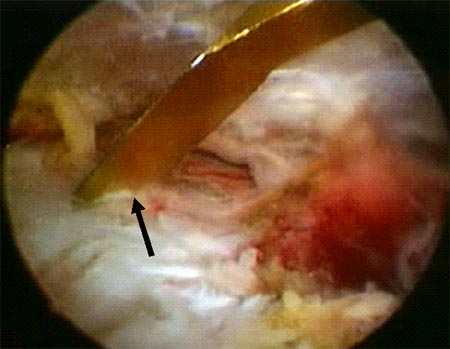

Si la reducción de los fragmentos es correcta en las imágenes por radioscopía, la fijación temporal de los fragmentos óseos con clavijas percutáneas es llevada a cabo. Posteriormente y según el tamaño de los fragmentos se utilizan tornillos canulados de 2.7 mm, 3,5 mm y/o 4.5 mm. Es importante remarcar nuevamente la no resección de los tejidos blandos (manguito rotador) de los fragmentos óseos. En 4casos de fracturas conminutas la reducción y osteosíntesis de los fragmentos fue lograda a través de los tejidos blandos y no del propio tejido óseo. Si la reducción de los fragmentos no es correcta la inspección del lecho de la fractura, primero a nivel articular y luego a nivel subacromial, es llevada a cabo con el fin de facilitar la misma mediante la remoción de tejidos interpuestos. En todos nuestros pacientes fueron colocados no menos de 3 tornillos de fijación (Fig. 1 y 2).

Figura 2D: Flecha negra: Clavija percutanea mantiene la reducción. Flecha Amarilla: línea de fractura./ Figura 2E: Osteosíntesis con tornillo canulado de 3.5 mm./ Figura 2F: Resultado. Escalón superior de 2 mm. Reparación de Bankart y SLAP.